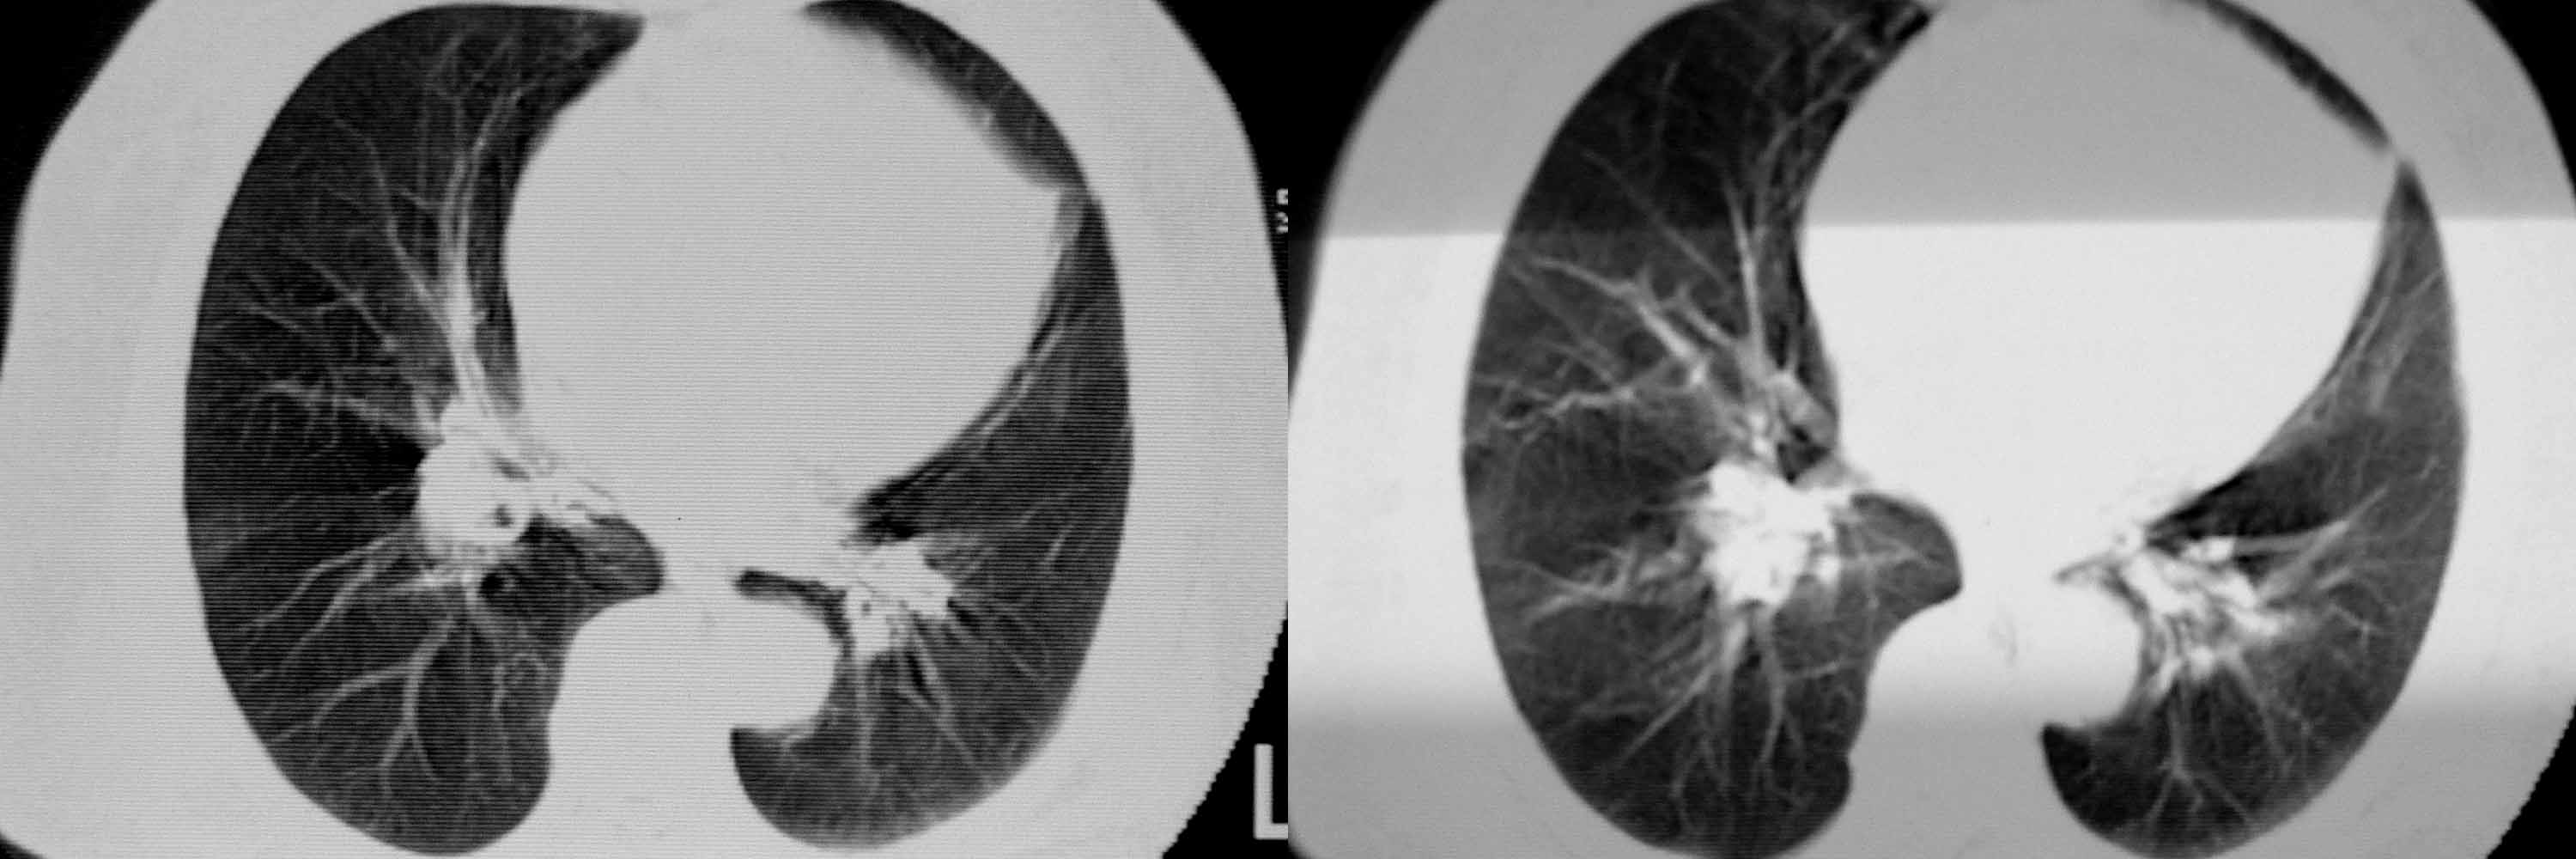

女78岁咳嗽咳痰无咳血平片报右上肺不张、慢支、肺气肿、请老师们帮忙看看,箭头所指是什么?是占位吗?有肺气肿吗?谢谢

箭头所指考虑血管影;纵隔内及双肺门区多发淋巴结钙化;不支持肺气肿。

箭头所指考虑血管影(头臂血管);纵隔内及双肺门区多发淋巴结钙化;不支持肺气肿。